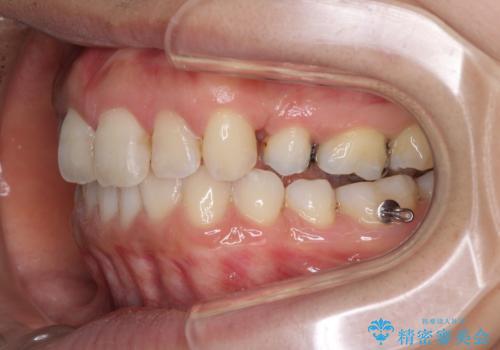

インビザラインにて抜歯矯正を行うと、高頻度で奥歯が咬み合わなくなります。

抜歯スペースが閉じてからも咬みにくさ改善のためマウスピース矯正を継続するため、治療期間は長期化します。